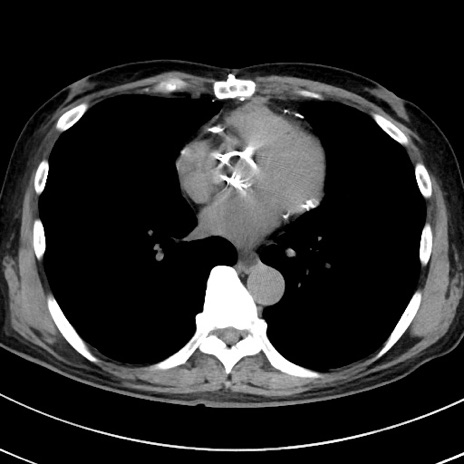

冠状断像

【症例】70歳代 男性

【主訴】腹痛・嘔吐

【現病歴】昨晩より、嘔吐・腹痛あり。今朝になっても嘔吐あり。来院。

【既往歴】心臓バイパス手術、開腹胆摘、腸閉塞

【身体所見】BP 107/71mmHg、HR 116/min、腹部:平坦、軟、下腹部に軽度圧痛あり。反跳痛なし。

【データ】WBC 15100、CRP 0.32